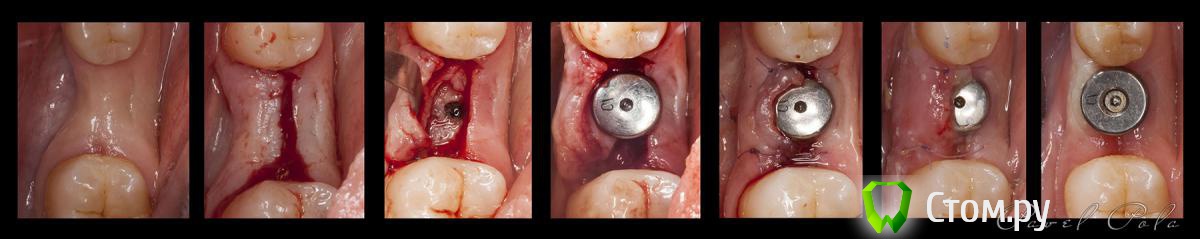

M@estro Опубликовано 21 сентября, 2014 Автор Поделиться Опубликовано 21 сентября, 2014 (изменено) Есть повод апнуть темку Справедливо выждав 9 месяцев с момента установки имплантата было принято волевое решение на установку ФДМ На самом деле, пацеинтка потерялась в дебрях ортодонтии, было не до меня. Учитывая,что нужно было убрать 1.8 - я решил,что это хороший шанс подсадить ССТ,чем,собственно,и занялись. Коллеги , Ваши замечания учёл - жду следующих http://s020.radikal.ru/i703/1409/e1/8932433a3170.jpg Трансплантат: http://s019.radikal.ru/i600/1409/4f/cbacdffe7acb.jpg Пост - оп: http://s019.radikal.ru/i607/1409/c6/9e289969d5de.jpg 1.5 недели : http://s61.radikal.ru/i171/1409/cc/c29fb5dd152c.jpg Изменено 21 сентября, 2014 пользователем M@estro 18 Ссылка на комментарий

kriokov Опубликовано 22 сентября, 2014 Поделиться Опубликовано 22 сентября, 2014 ССТ с язычной не увидел с язычной, только со щечной увидел.Хорошо все, дополнительный обьем кинули туда, где он был нужен, судя по фоткам Ссылка на комментарий